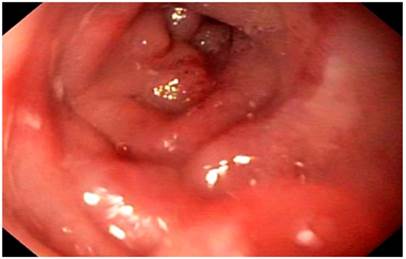

On physical examination, signs of dehydration were observed, with no other positive findings. In view of the history and symptoms described, an endoscopy of the upper digestive tract was performed. Food impaction was observed at the level of esophagojejunal anastomosis (Figure 1). A foreign body was removed, and an anastomosis was found, with no signs of tumor relapse. However, 10 cm from the anastomosis, a stenosis zone of 40% of the lumen was found, with a concentric decrease of the lumen due to a circumferential edema of the mucosa (Figure 2), which allowed the equipment to get in with a slight resistance, and biopsy samples were taken from the area.